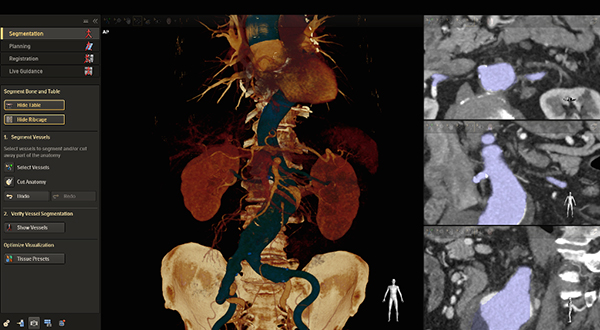

VesselNavigator オペレーション画面の一例

「VesselNavigator」はライブX線透視画像と,予め取得した患者様の血管構造の3D MRI画像またはCT画像を融合するもの。その結果得られる色分けされた3D血管像により,リアルタイムの画像ナビゲーションが改善され,造影剤を使用してのX線造影像を頻繁に取得する必要が減り,複雑な血管走行に沿ったカテーテル操作もよりスムーズに実施することが可能になる。「VesselNavigator」により造影剤の使用量を70%*4,処置時間を18%*5 低減するとの最近の研究論の発表もあり,これまで以上に患者さんに優しく効率的で対費用効果の高い血管疾患治療に寄与することが明らかにされている。